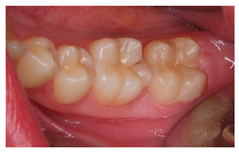

The question from scenario 1a was open-ended; participants were asked to provide a diagnosis of a lesion in tooth 3.6. A total of 41.5% of the surveyed students considered that the image presented a retentive pit/fissure or stained pit/fissure; 39% of them answered that the image exhibited a carious lesion. The answers “healthy”, “early carious lesion”, and “chronic carious lesion” were less frequent: 2.4%, 9.8%, and 7.3%, respectively. For this question, the correct answers were: “retentive pit/fissure or stained pit/fissure” and “chronic carious lesion”. “Healthy” and “carious lesion” were considered as incorrect. Thereby, 48.8% of the surveyed students answered correctly (Figure 1).

For scenario 1b, students were required to order different complementary diagnostic tests from more to less adequate for the diagnosis of the presented case. The most prevalent answer, “bitewing X-ray” (51.2%), “periapical X-ray” (12.2%), and “no complementary diagnostic test is required” (36.6%). The latter was the option considered as correct (Figure 1).

In a similar manner, the surveyed students were asked to order different therapeutic options in scenario 1c. The option “oral health instructions and 6-month follow-up visit” was selected by 51.2% of the participants. This answer was considered as correct Additionally, 9.8% of the students would perform a “pit and fissure sealing”, 7.3% would opt for a “2-year follow-up visit”, and 2–4% would carry out a resin-based obturation/filling (Figure 1).

The results from the present study confirmed that approximately half of the last-year students from the degree in dentistry proposed a correct diagnosis for the first clinical scenario, following the criteria established by The International Caries Consensus Collaboration or ICCC [33], in which the extension and activity of the lesion are considered. The question was open-ended, and a high percentage of participants answered “caries”, without providing more details regarding the activity of the lesion.

As advised by the ICCC, the diagnosis of caries, nowadays, has to be based on the visual clinical exploration and the evaluation of individual risk of caries development [34]. Diagnostic tests will act as supporting material for the determination of the extension of the lesion and to control its progression over time. The majority of students selected, as a complementary test, performing a bitewing X-ray to confirm de diagnosis. This could be considered as an indication for “overdiagnosis”, as this test, in the case of an inactive carious lesion limited to the superficial enamel on the occlusal surface, does not provide any additional help to the diagnosis [13]. This tendency to use complementary tests could be explained by the clinical inexperience of the students and by the excessive trend to support diagnosis on complementary tests (Figure 1).

Currently, there is a great tendency towards the restoration of lesions limited to the enamel, although the scientific evidence supports other non-invasive alternatives for the control of these lesions [35]. According to these criteria, an inactive carious lesion categorized as ICDAS II (clinical scenario 1c) should not receive any restorative treatment, but only require oral health instructions and control of individual risk factors, together with follow-up control visits [35]. Interestingly, the percentage of students who correctly answered the therapeutic approach in scenario 1c (51.2%) was higher than those who correctly answered the diagnosis in scenario 1a (48.8%). This difference may have been due to the fact that students who misdiagnosed scenario 1a as “healthy” or “early carious lesion” may have selected “oral health instructions and 6-month follow-up visit” as a therapeutic approach. However, a little more than half of the students selected this non-invasive therapeutic alternative. It should be highlighted that up to 41.7% of the students would place a resin composite restoration, which in this case is considered as an “overtreatment”. Available systematic reviews among the literature regarding the treatment for early carious lesions found a significative proportion of dentists who would propose restorative treatments upon carious lesions for which minimally invasive technique are indicated [30,32]. Thus, it is necessary to orient dental students into a less invasive approach, taking into account the natural progression of the disease, and treating lesions according to their extension and carioactivity. Because the influence of the type of undergraduate formation influences the postgraduate therapeutic attitude [36].